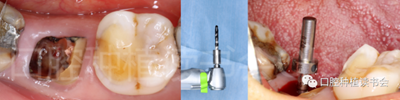

5.3.1 使用球鉆及帶有定深器的先鋒鉆在根分叉上方定點(diǎn)、定深,確定方向(圖14)。

圖14 選擇在殘根根分叉上方定點(diǎn),先鋒鉆預(yù)備方向。

5.3.2 逐級(jí)預(yù)備種植窩洞后,側(cè)切鉆分根,微創(chuàng)拔除殘根,探查頰、舌側(cè)骨板完整,仔細(xì)搔刮拔牙窩,生理鹽水沖洗(圖15)。

圖15 微創(chuàng)拔牙后確認(rèn)種植窩洞位于牙槽間隔內(nèi)。